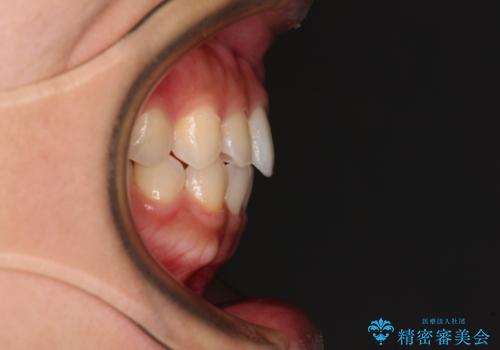

- 上顎前歯の叢生を気にして来院された患者様です。

下顎前歯や上下奥歯の咬み合わせには殆ど問題がないため、上顎前歯のみを矯正する治療を提案しました。

ワイヤー装置でもインビザラインでも可能でしたが、前歯のみをきれいに排列するのであればインビザラインの方が仕上がりが良いので、インビザライン・ライトにて治療を行うこととしました。